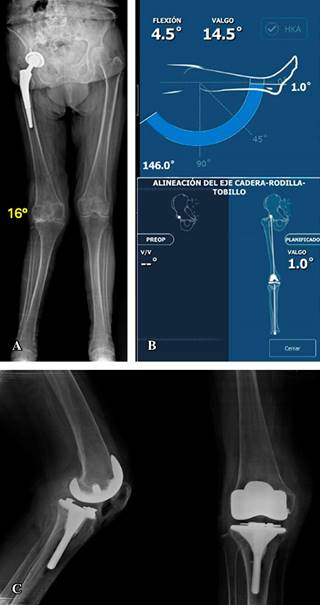

Dieciséis casos presentaron deformidad en valgo (Figuras 2 y 3) con un promedio de 11.88o de deformidad. En cuatro casos la alineación final fue en varo con un promedio 1.87o; en nueve la alineación final fue con un valgo promedio de 1.66o y en tres casos la alineación fue neutra. El cambio en los grados promedio de la serie entre la deformidad inicial y la alineación final fue estadísticamente significativo (p = 0.005) en el análisis de covarianza.

Figura 2: A) Eje mecánico de los miembros inferiores de un caso con un vástago de longitud convencional de artroplastía no cementada de cadera derecha y deformidad angular de rodilla en valgo de 16o en la rodilla ipsilateral. B) Análisis de movilidad y alineación postoperatoria con cirugía robótica (rango de movilidad de 1 a 146o) y alineación final en valgo de 1o. C) Radiografía postoperatoria con prótesis de rodilla estabilizada posterior y vástago tibial de 80 mm.